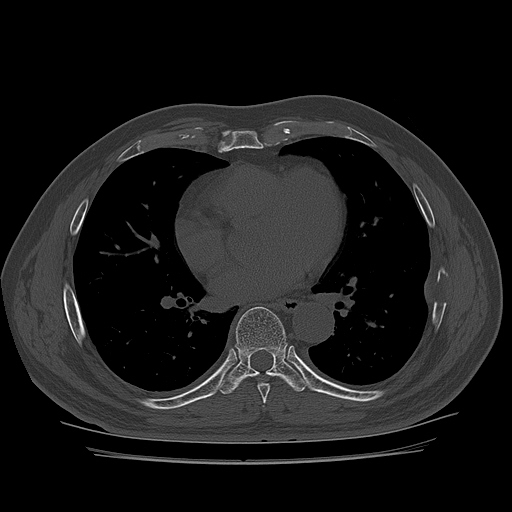

lin longitudinal scan of 7th. rib, appearance of bony mass(protrusion) just like callus(image 1).

on moving of prove a little, there is bony protrusion(osteoblastic lesion) and hypoechoic(osteolytic)  lesion(image 2, 3, 4).

CT ; metastacic mass at rib and adjacent lung

CT image